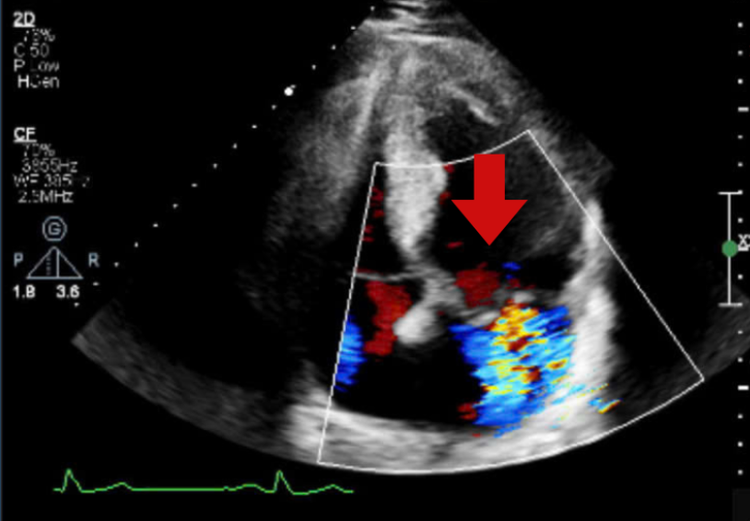

Khi tiến hành siêu âm Doppler tim toàn diện, bác sĩ phát hiện van hai lá bị sa và hở nhiều, khiến máu trào ngược trong tim. Tình trạng này kéo dài đã làm các buồng tim bên trái giãn to, chức năng co bóp của tim bắt đầu suy giảm. Đây là những bất thường khó có thể phát hiện nếu chỉ siêu âm nhanh hoặc đánh giá tổng thể, mà cần khảo sát kỹ từng vùng cơ tim ở nhiều góc độ khác nhau.

khoe-manh-tim1.png

Siêu âm tim ghi nhận hình ảnh dòng màu hở van hai lá - Ảnh BVCC